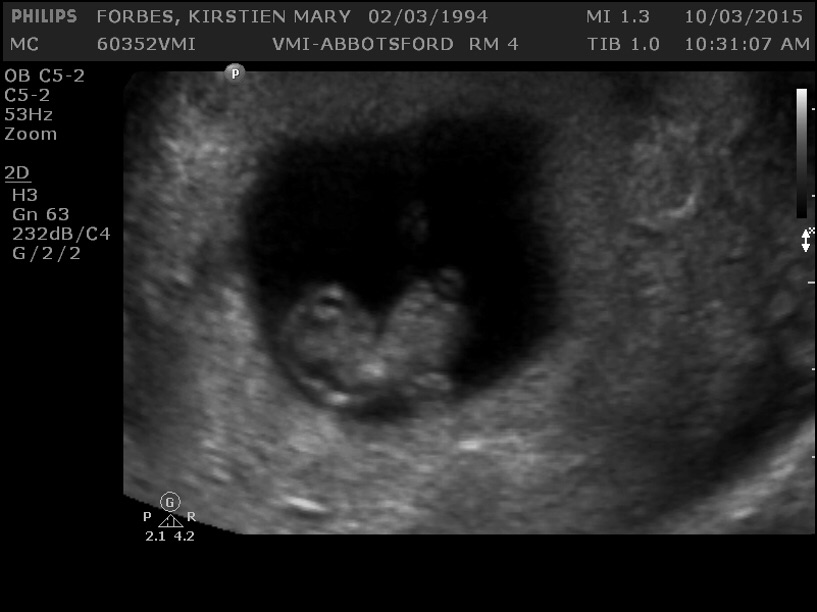

I wasn't going to post mine, but what the hell. Here is my little jellybean a week ago, at 8 weeks and 6 days. They gave me a regular-looking ultrasound picture and two of these freaky 3D ones.